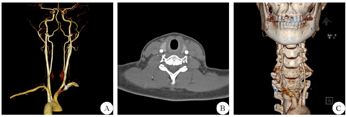

患者女性,28岁,因"一过性晕厥致头皮擦伤7 d"于2018年5月2日就诊于我科门诊。7 d前,患者在弯腰取物过程中,突发晕厥倒地,呼之不应,几分钟后神志自行转清,但仍自觉轻度头晕、头痛,头皮局部擦伤。近10余年间,患者晕厥多次发作,每次持续3~5 min,均能自行缓解,曾于广州、重庆、成都、泸州等地的三甲医院就诊,颅脑MRI、头颈部MRA、头颈部CTA、心脏彩超、颈部血管彩超、视屏脑电图、动态心电图、血常规、血电解质、随机血糖、肝肾功、心肌酶、血绒毛膜促性腺激素等检查均未明确病因。本次门诊检查见:右侧颞部头皮轻度压痛,头皮擦伤部位已结痂,专科体检未见明显异常。血红蛋白:121 g/L;随机血糖6.5 mmol/L。颈部CTA:双侧头颈部动脉未见异常狭窄或扩张改变,右侧椎动脉V1段绕行C6横突孔前缘进入C5横突孔(图1)。转颈经颅多普勒(TCD)(中国南京科进实业有限公司产品,型号:KJ-2V6M)检查:患者平卧位头颈左转约90°后,出现明显头晕症状,无法配合检查;头颈左转60°检查发现,右侧椎动脉的血流平均速度降低48%,基底动脉的平均速度降低30%(表1)。由此,明确诊断为BHS,患者选择保守治疗,并遵嘱左侧转颈尽量小于45°。自2018年6月至2020年8月,每月1次电话随访,患者无晕厥发作。

A:颈动脉3D重建;B:横断面图像,显示右侧椎动脉在C6右椎间孔外,左侧椎动脉在C6左椎间孔内;C:椎动脉及颈椎3D重建,显示右侧椎动脉V1段绕行C6横突孔前缘进入C5横突孔